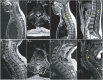

Figure 3. Spinal Cord MRI Features of Patients With Anti-GFAP Antibodies

Spine MRI of patients with anti–glial fibrillary acidic protein (GFAP) antibodies show longitudinally extensive (A.a) and most prominent centrally (A.b) abnormal T2 hyperintensity accompanied by central canal enhancement (A.c, arrowheads) and leptomeningeal enhancement (A.d, arrowheads), holocord longitudinally extensive T2 hyperintensity (B.a and B.b), and longitudinally extensive T2 hyperintensity (C.a) accompanied by patchy enhancement (C.b, arrowheads).